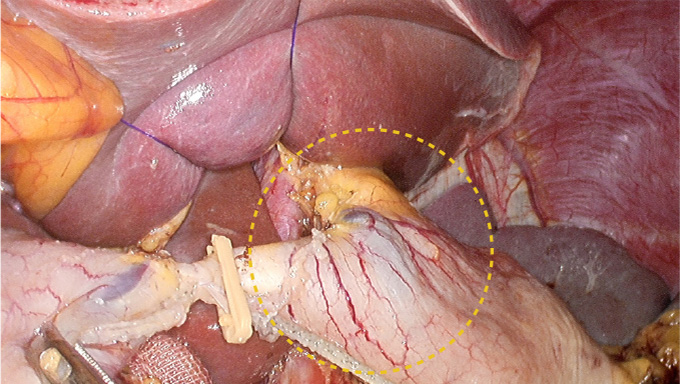

By processing specific color signals, the shapes of blood vessels are highlighted, enabling the surgeon to clearly distinguish tissue layers and blood vessel directions, reducing the risk of bleeding